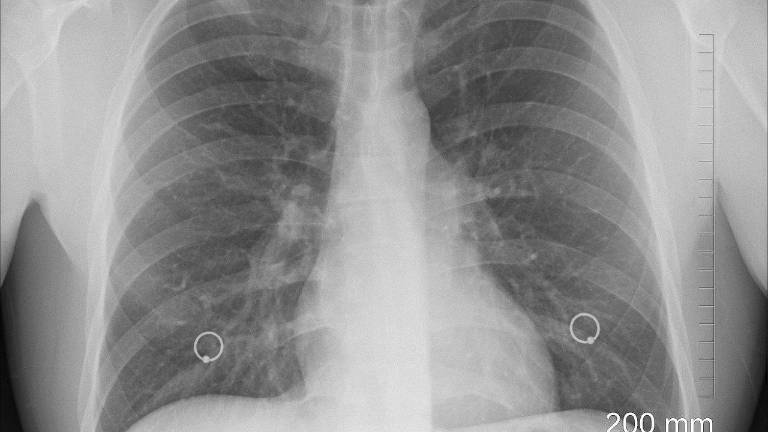

Mamografía, Ecografía y Biopsia Core se realiza en casi todos los casos para diagnóstico de cáncer. Tenemos además mamografía tridimensional (tomosintesis), ampliación focal por mamografía, resonancia magnética, pruebas genéticas, biopsias por estereotaxia, biopsias con arpón, etc. Hoy en día el diagnóstico y tratamiento es individualizado para cada mujer y cada caso, por eso la importancia de acudir al especialista que es el mastólogo.